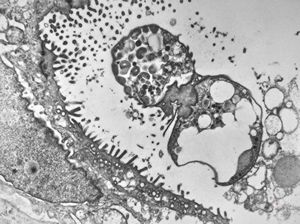

M,82y. | Helicobacter pylori - antrum pylori